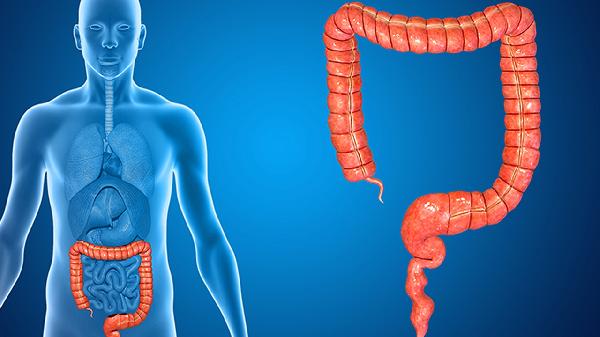

先天性腸旋轉不良主要由胚胎期腸管旋轉固定異常引起,常見原因包括中腸旋轉不全、腸系膜固定缺陷、臍帶發育異常、遺傳因素及母體環境干擾。

胚胎第6-10周中腸未完成270度逆時針旋轉,導致盲腸停留于右上腹,腸系膜根部縮短。這種解剖異常可能引發腸扭轉或十二指腸梗阻,患兒出生后常出現膽汁性嘔吐等急腹癥表現。

正常發育中腸系膜應固定于后腹壁,若固定過程受阻則形成游離腸系膜。這種缺陷使腸道活動度異常增大,約60%病例伴隨中腸扭轉風險,需通過超聲檢查腸系膜上動脈位置進行診斷。